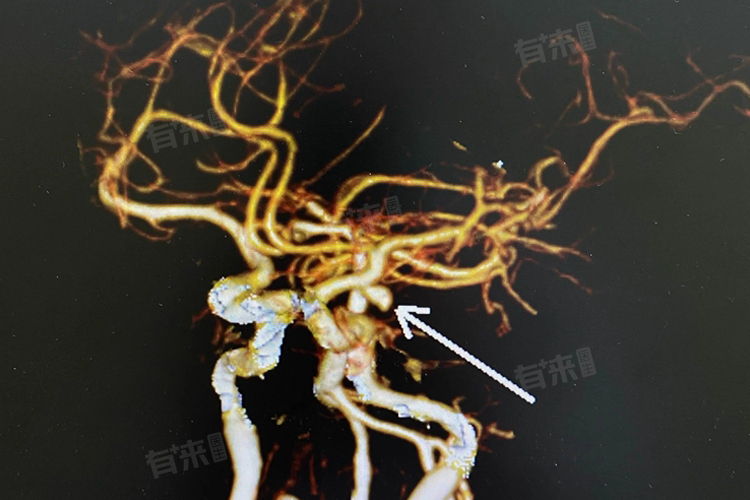

脑动脉血管瘤的症状复杂多样,且破裂后病情凶险,死亡率和致残率极高。因此,一旦出现上述症状,尤其是剧烈头痛、意识障碍等严重症状时,应立即就医,进行头颅CT、磁共振血管造影等检查,以明确诊断并及时治疗。